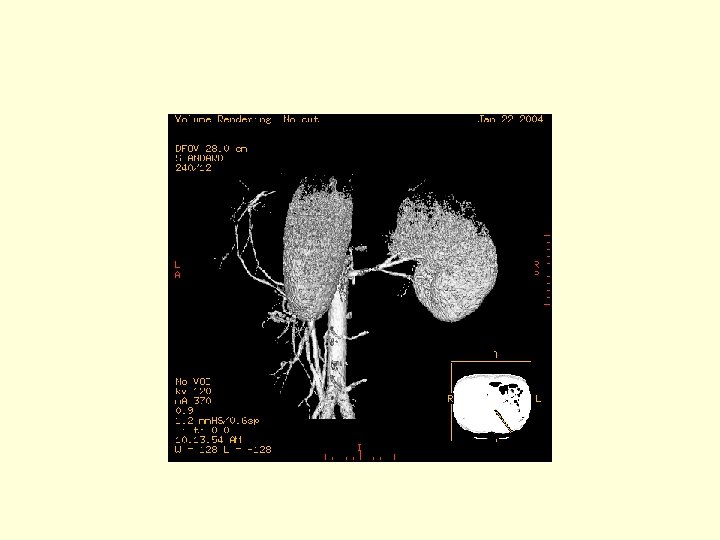

This is a 3 D image showing the branches of the SMA.

This is another 3 D image showing the vasculature of the SMA. Click through the next 20 frames to rotate the image.